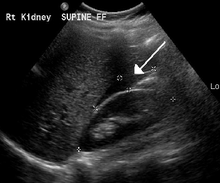

A small amount of anechogenic free fluid in the rectouterine pouch is commonly found in both intrauterine and ectopic pregnancies.[1] The presence of echogenic fluid is estimated at between 28 and 56% of women with an ectopic pregnancy, and strongly indicates the presence of hemoperitoneum.[1] However, it does not necessarily result from tubal rupture, but is commonly a result from leakage from the distal tubal opening.[1] As a rule of thumb, the finding of free fluid is significant if it reaches the fundus or is present in the vesico-uterine pouch.[1] A further marker of serious intra-abdominal bleeding is the presence of fluid in the hepatorenal recess of the subhepatic space.[1]